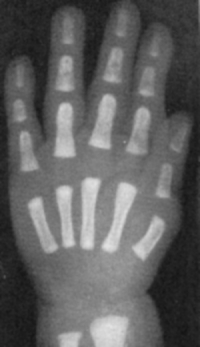

Sexo Feminino

Recém-Nascido